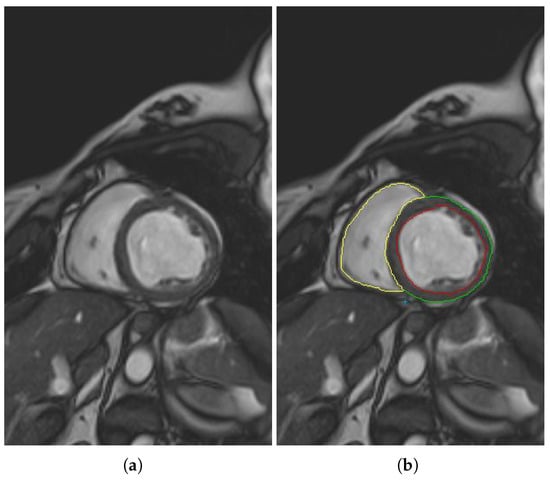

- The different MSERs are detected in a centered ROI of each input image by the use of OpenCV [23]. As the LV cavity is normally represented by a circular shape, the centroid of each MSER detected is computed in order to automatically identify the left ventricle cavity anywhere in the image and for applying the convex hull.

- The previous application of the convex hull allows a second refining to optimize the search process of the external layer and the trabeculae areas. The parameter e-expand is redefined and adjusted to accurately determine the external layer of the compact zone, thanks to plotting several lines from the centroid of the LV to reach the points of the external layer. This parameter establishes the distance of the lines between the centroid of the LV cavity and the possible space where the external layer can be found, taking into account the particular features of genetic cardiomyopathies. We optimized the parameter e-expand for different situations or possible cardiomyopathies.